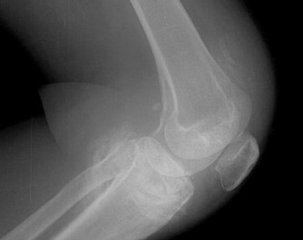

滑膜炎能否彻底治疗是很多患者都非常关心的问题。那么什么是滑膜炎呢?滑膜炎是滑膜受到刺激产生炎症,造成分泌液失调形成积液的一种关节病变,长期以来,影响患者的正常生活,工作,带来了很多麻烦,有些患者四处求医,反复发作,痛苦不堪,甚至心理蒙上一层阴影。

滑膜炎症状主要是关节肿胀,其次是疼痛,功能障碍,肌萎缩,所以如果发现有类似的情况应及时就诊,明确诊断,排除其它因素的可能,仔细检查,以防漏诊,避免延误病情。有些患者在没有正确诊断下,盲目的治疗,丧失了较好治疗时机。

经确诊后及时正规 的治疗是很关键的,滑膜炎早期一般主要是急性期,采用西医方法,比如:激素、抽液、冲洗、抗生素等治疗,可以取得满意的疗效,若治疗不彻底,错过较好治疗期,炎症逐渐转化为慢性期,反复积液滑膜肥厚、粘连,影响到关节的功能问题。